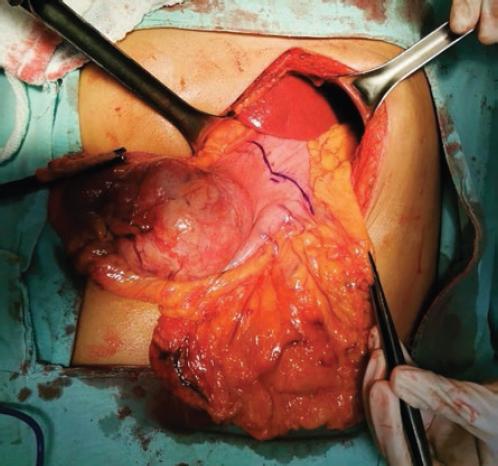

Mujer de 53 años con antecedente de hipertrigliceridemia en tratamiento con fibratos. Es referida por historia de 3 años de evolución de pérdida de peso y saciedad temprana, progresivamente se agrega plenitud posprandial y masa palpable en el epigastrio, motivo por el que se realiza una tomografía contrastada toracoabdominal que reporta una lesión homogénea de contorno bien delimitado en la pared del cuerpo gástrico, de 7.5 × 5.7 × 5.8 cm (Fig. 1). Se realiza endoscopia superior y se encuentra una lesión subepitelial umbilicada en la curvatura menor a nivel de la unión del cuerpo con el antro gástrico (Fig. 2); se complementa con sonografía endoscópica (Fig. 3), con hallazgo de una lesión sólida hipoecoica en la pared gástrica que se origina en la capa muscular externa, bien circunscrita, con medidas de 4.9 × 4.3 cm. Se toman biopsias por aspiración con aguja fina, con reporte de citología transprocedimiento de tumor fusocelular. Se decide el manejo quirúrgico por sospecha de tumor del estroma gastrointestinal (GIST, gastrointestinal stromal tumor) y por la sintomatología en ese momento (Fig. 4). Durante la intervención se encuentra una tumoración firme en la curvatura menor que se extiende al antro gástrico. Se realizan gastrectomía distal (Fig. 5) y anastomosis gastroyeyunal en Y de Roux, sin complicaciones durante el procedimiento.

Figura 4 Exploración quirúrgica de la cavidad abdominal exponiendo la porción distal del cuerpo gástrico, el antro gástrico y el omento mayor.

Figura 5 Resección quirúrgica de la porción distal de estómago con una tumoración firme en la unión del cuerpo y el antro gástricos.